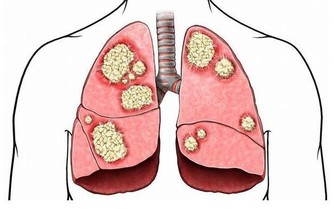

肺癌是“癌症之王”,是人類死亡的頭號殺手。肺癌的發病率男性多於女性,城市多於農村。

肺癌並非吸煙一族的專利,經常接觸二手煙、做飯的女性也是肺癌的高危人群。肺癌的致病因素比較複雜,空氣污染、環境因素、粉塵、刺激性氣味環境、遺傳史等等都是導致肺癌的致命因素,它就像一種慢性病一樣,在某種致病因素的長期刺激下,正常細胞會發生癌變,慢慢地形成腫瘤。據了解,閆懷禮在河北涿州拍攝一部叫《俏羅城》的電視劇。當地的蒼蠅、蚊子特別多,當時有一場戲拍戲的現場噴灑了很多敵敵畏,很多人都因為濃重的味道離開了,當時閆懷禮嗅覺不好感覺不到,長時間處在敵敵畏濃重的環境裡面,拍戲空擋還在那裡休息,好友六小齡童分析這是他患病的誘因之一,再加上多年拍戲工作太過勞累,閆懷禮才患上了肺癌。

肺癌幫介紹,肺癌是一種高隱藏性癌症,潛伏期最長達10年。早期沒有明顯症狀,當有的人發現腰痛、腿疼、肩痛的時候,可能肺癌已經發生了轉移,但前期沒有任何症狀。這樣的例子生活中很常見,也給我們的健康敲響了警鐘,每年定期體檢和癌症篩查是很有必要的。